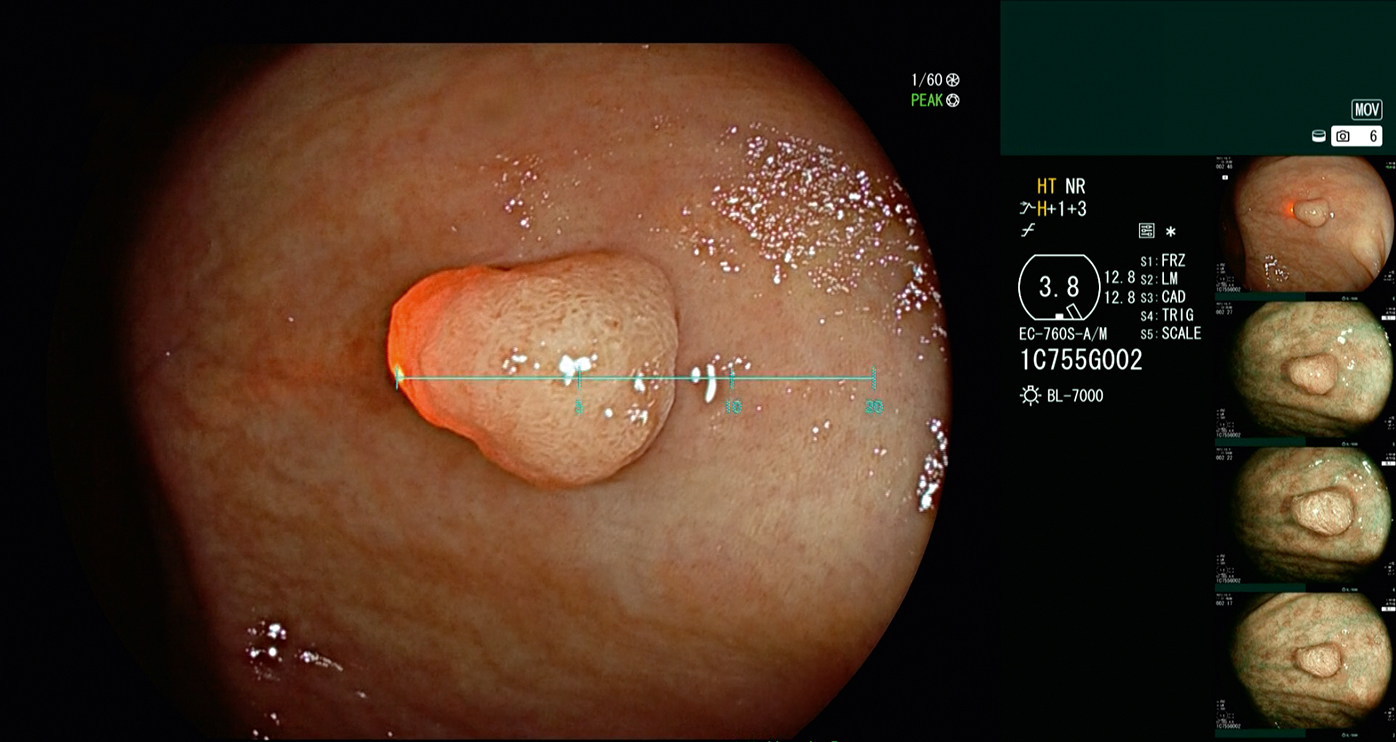

Fujifilm has developed SCALE EYE, a function designed to aid endoscopists in estimating the size of lesions in the colon. By simply pressing the endoscope switch, SCALE EYE is activated to support the endoscopist to determine the size of the lesion within the endoscopic field of view.

The SCALE EYE system includes the newly developed endoscope EC-760S-A/M, L, which is equipped with a class 1 laser. The laser point is visible within the endoscopic image. The position of the laser point changes relative to the distance between the tip of endoscope and the object. Depending on this laser point position, the scale interval size adjusts automatically.

- SCALE EYE is a Fujifilm brand name of function to support size estimation by virtual scale. To enable SCALE EYE, the EC-760S-A/M and EC-760S-A/L colonoscopes which are equipped with a red laser are used in combination with the “Endoscopy Support Program EW10-VM01.”

Scale size is selectable from 5mm, 10mm, and 20mm, and the activation and the deactivation of the function can be simply operated by the endoscope switch.

The virtual scale is displayed on the same endoscopic monitor in real-time and does not require a separate monitor.